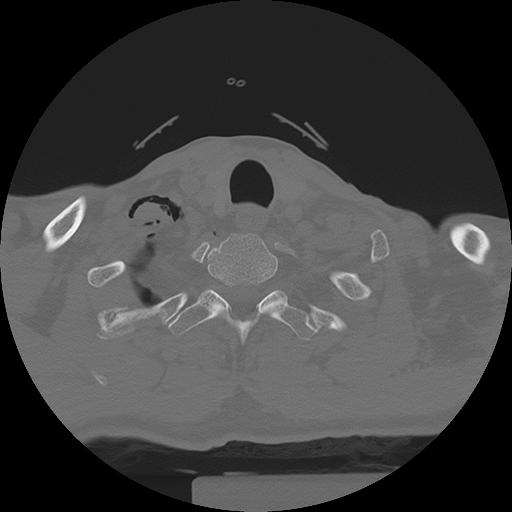

11 HUESO,,Axial,2.0,HUESO,,